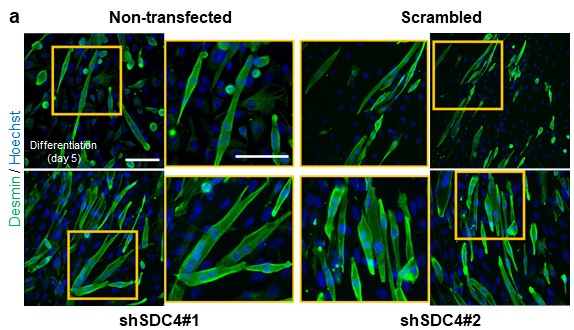

After injury, the skeletal muscle is capable of regeneration. A population of resident stem cells (i.e., satellite cells) accounts for skeletal muscle plasticity, maintenance, and regeneration. Satellite cells are mitotically and physiologically quiescent in healthy muscles until stimulated by local damage. Accordingly, after a skeletal muscle injury, an intense regenerative program is initiated. The activated satellite cells migrate to the site of injury and become committed myoblasts, after which cell–cell fusion occurs, eventually creating multinucleated syncytium. To treat skeletal muscle diseases, muscular dystrophies, muscle mass loss associated with ageing or cancer, and to improve regeneration after sports injuries, it is essential to elucidate the signalling processes that influence the proliferation, differentiation and fusion of myoblasts formed by activation of skeletal muscle myogenic stem cells.

We found that silencing SDC4 (syndecan-4), a key proteoglycan, disrupts the polarization of migrating myoblasts (satellite stem cells). SDC4 knockdown abolished the Ca²⁺ gradient and centrosome reorientation, leading to reduced cell motility, migration distance, speed, and directional movement. We revaled futher changes in the actin cytoskeleton, including reduced branch numbers and lengths, highlighting SDC4's role in cell migration, particularly during muscle development and regeneration. For future studies we would like to know what role does SDC4 play in modulating cell motility.

Rhabdomyosarcoma, the most common soft tissue sarcoma in children, arises from skeletal muscle cells that fail to differentiate terminally. As a result, instead of forming mature muscle tissue, the tumor cells grow uncontrollably. Studying how muscle cell differentiation is disrupted in RMS could help identify potential treatments that target these molecular mechanisms, either promoting normal muscle formation or preventing tumor cells from becoming more undifferentiated and cancerous.